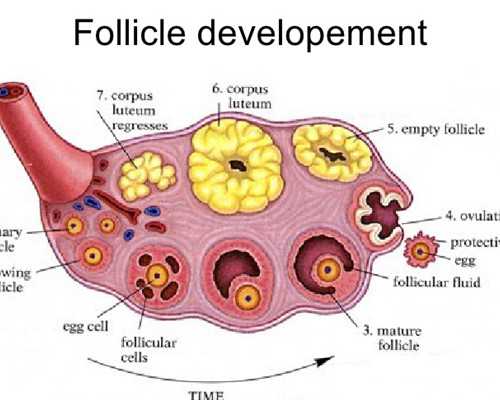

1、卵巢垂體功能檢查:了解女方排卵日期、有無排卵日期和有無排卵功能障礙。可通過基礎體溫測定、宮頸粘液檢查或性激素測定來進行檢查。